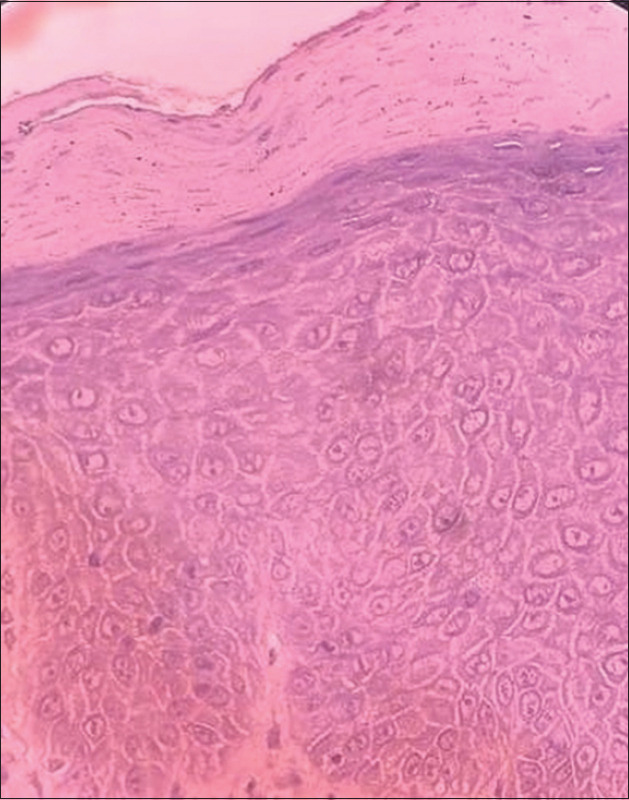

Inflammatory linear verrucous epidermal nevus (ILVEN) is a variant of keratinocytic epidermal nevi. In contrast to noninflammatory epidermal naevi, ILVEN is less common, typically erythematous, and persistently pruritic. It usually appears at birth or in early childhood and follows a linear distribution along Blaschko's lines. Genital or perigenital involvement is relatively rare. We report a case of ILVEN on the labia majora of an 11-year-old female. ILVEN usually presents on extremities and trunk, but is uncommon on the genitalia.